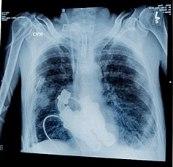

Heart Stop Beating is the story of Billy Cohn & Bud Frazier, two visionary doctors from the Texas Heart Institute, who in March of 2011 successfully replaced a dying man's heart with a 'continuous flow' device they developed, proving that life was possible without a pulse or a heart beat.